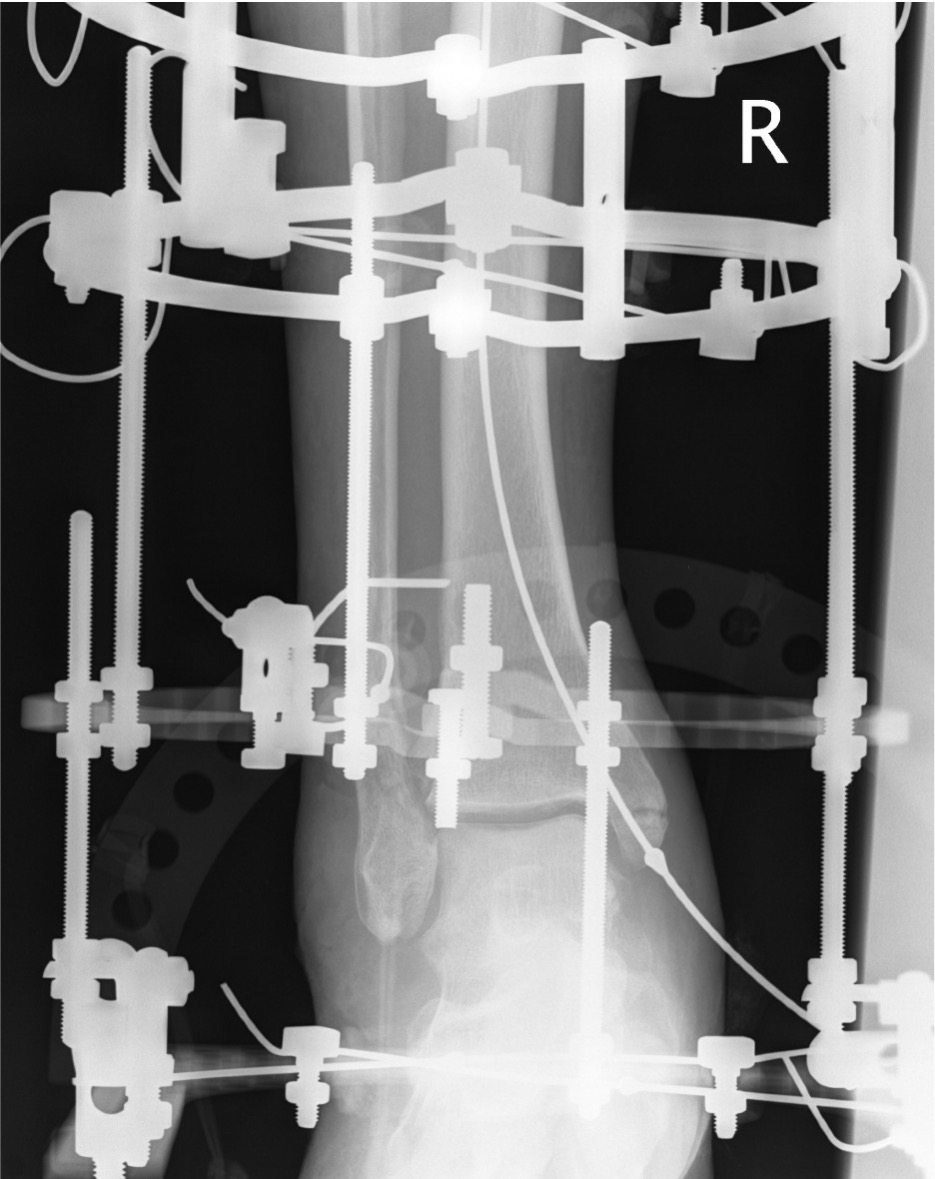

External fixation

Unstable reduction / swelling / poor skin / blisters

Ankle ex fixANkle ex fix